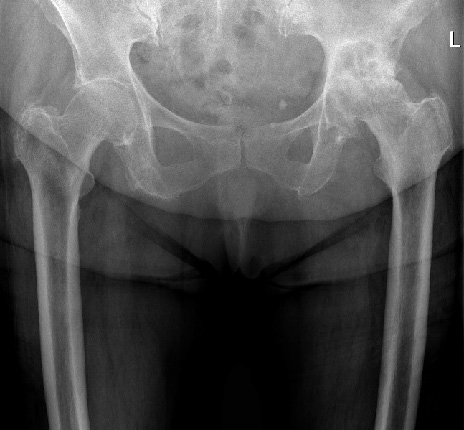

Streszczenie Choroba zwyrodnieniowa stawów biodrowych jest bardzo częstym i poważnym problemem zdrowotnym wśród osób powyżej 65. roku życia. W przypadku znacznego zaawansowania choroby i po wyczerpaniu możliwości leczenia zachowawczego przeprowadza się zabieg endoprotezoplastyki. Najpopularniejszym badaniem przed wszczepieniem i po wszczepieniu endoprotezy jest klasyczne RTG (Classic Roentgenodiagnostics) porównawcze stawów biodrowych. Ocena stanu po endoprotezoplastyce stawu biodrowego wymaga wykonania bardzo wysokiej jakości radiogramów. Zgodnie z filozofią optymalizacji w…